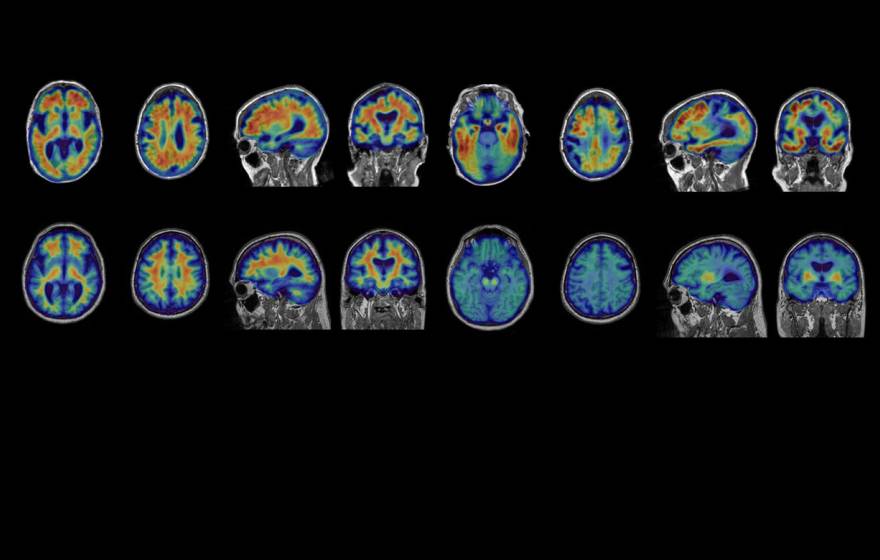

An allergy drug showed promise for MS. Could they prove it?

Years of scientific sleuthing leads to breakthroughs in multiple sclerosis.